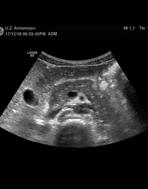

Op de beelden was te zien dat de afwijking in de lever goedaardig was, waardoor een operatie niet noodzakelijk bleek.

Dankzij de bijkomende MRI kwamen de artsen te weten dat er niet één, maar drie letsels waren.

Letsel bleek goedaardig Er was een tweede en derde tumor

Prof. dr. Dirk Ysebaert, diensthoofd hepatobiliaire, transplantatie en endocriene heelkunde: ‘In een regi onaal ziekenhuis ontdekten artsen bij een vrouw van 36 een levertu mor. Ze werd doorverwezen naar onze dienst voor een leveroperatie.’ Samen met radioloog dr. Bart Op de Beeck, kliniekhoofd Body imaging, bekeek Ysebaert de oorspronke lijke beelden. ‘We besloten om niet meteen te opereren, maar eerst te bepalen of de afwijking goed of kwaadaardig was, via een MRI met levercontrastmiddel.’

Uit de nieuwe scan bleek dat het

om een goedaardige afwijking ging. ‘In dat geval was het niet nodig om de dame te opereren. Een goedaardige afwijking kan in principe geen kwaad. We hebben de dame opgevolgd, en ook na drie jaar was de afwijking ongewijzigd.’ Een grote opluchting voor de vrouw in kwestie. Ysebaert: ‘Bij een operatie zouden we bijna de helft van de lever hebben moeten wegnemen.

Dankzij de geavanceerde beeld vorming die we als universitair ziekenhuis kunnen aanbieden, hebben we dus een zware operatie kunnen vermijden.’